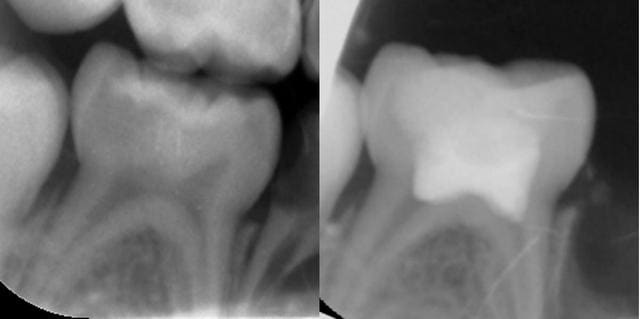

PULPOTOMIE DE DENT TEMPORAIRE

Éviction de la pulpe camérale.

La dentine d'une dent temporaire a des tubulis plus larges et nombreux qu'une dent permanente. En cas d'une atteinte dentinaire moyenne à profonde, la pulpe camérale est contaminée et donc potentiellement inflammatoire ou nécrosée.

On considère que, par contiguïté, la pulpe camérale est plus contaminée que la pulpe radiculaire. La pulpe radiculaire, à distance et ayant un fort potentiel de défense, a moins de probabilité d'un état pathologique. Suite à l'éviction de la pulpe camérale, l'observation clinique des moignons pulpaires radiculaires est primordiale : ceux-ci doivent avoir un aspect sain pour que l'on puisse les conserver.

- Obturation de la chambre : idéalement MTA ou biodentine. L'IRM (ZnO/Eugénol) est un bon compromis cout/efficacité).

PRONOSTIC : excellent. 95% de succès. Les échecs possibles sont la nécrose de la pulpe radiculaire ou des résorptions radiculaires. Les causes d'échec sont : erreur de diagnostic clinique de la pulpe radiculaire, contamination par salive ou débris carieux.